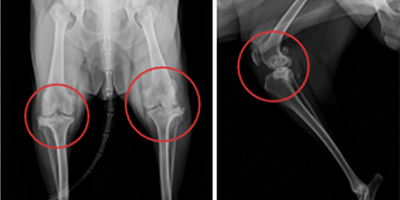

인공 무릎관절 치환술 Total Knee Replacement (TKR) 슬관절

슬관절 인공관절 수술은 중증의 골관절염이나 이전 수술(TPLO, TTA 등) 이후 심한 관절 변형 또는 강직으로 일상적인 보행이 어려운 경우에 시행됩니다.

특히 슬개골 탈구, 십자인대 파열 등으로 반복적인 수술과 관절 손상이 누적된 환자에서 고려됩니다. 과거에는 관절 고정술(stifle arthrodesis)이 대안이었으나, 정상적인 관절 각도 유지와 보행 기능 회복을 위해서는 인공 무릎관절 치환술이 더 나은 선택이 될 수 있습니다.